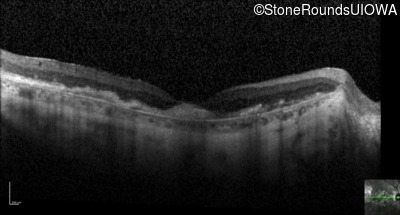

Optical Coherence Tomography - Left - 20/160 -1

Exemplar / OCT Stack